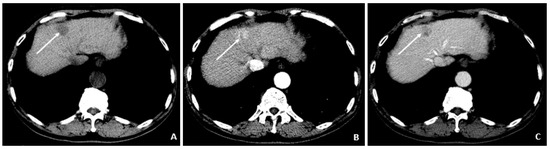

Figure 1.

MRI at the time of diagnosis of HCC (December 2009). (A) The coronal T2-weighted image shows a mildly heterogeneous mass in the left hepatic lobe (arrow), corresponding to hepatocellular carcinoma. (B) The axial T1-weighted fat-suppressed arterial-phase postcontrast image shows faint foci of hyperenhancement within the lesion, characteristic of HCC.